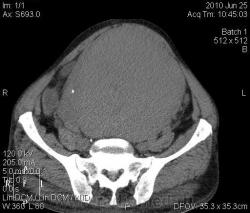

КТ. Забрюшинная опухоль. Лейомиосаркома. Вторичный гидронефроз.

Мужчина 79 лет, долгое время не обращался за медпомощью. Видимое внешне образование брюшной полости. По УЗИ: опухоль брюшной полости, двусторонний гидронефроз. Гемоглобин 136, СОЭ=12, креатинин крови 230. На КТ: плотность преимущественно 40 ед.Н, есть очаги пониженной до 12 ед.Н плотности. Увеличения лимфоузлов, костной деструкции не выявлено. Печень однородна. Не контрастировали (отказ пациента). Заключение: образование забрюшинного пространства (лейомиома?). Оперирован, лейомиосаркома.

По картинкам получается, что опухоль растёт из «задней» стенки моч. пузыря. В этом случае, понятно, она – забрюшинная и гидронефроз вторичный да двусторонний понятен также.